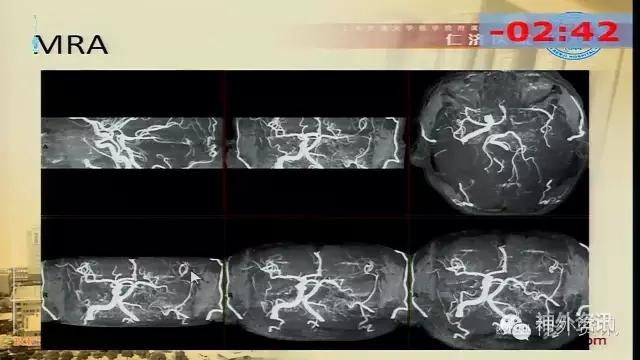

万杰清教授:慢性颈动脉闭塞再通技术及临床效果